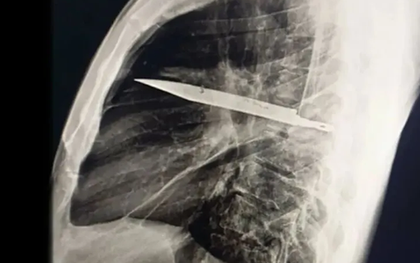

Người đàn ông mang "thứ này" trong lồng ngực suốt 8 năm mà không hề hay biết

Một trường hợp y khoa gây sốc vừa được ghi nhận tại Tanzania: một người đàn ông 44 tuổi đến bệnh viện vì vùng ngực dưới núm vú phải chảy dịch mủ kéo dài 10 ngày. Bệnh nhân không hề sốt, không khó thở, cũng không có biểu hiện đau đớn nào bất thường.